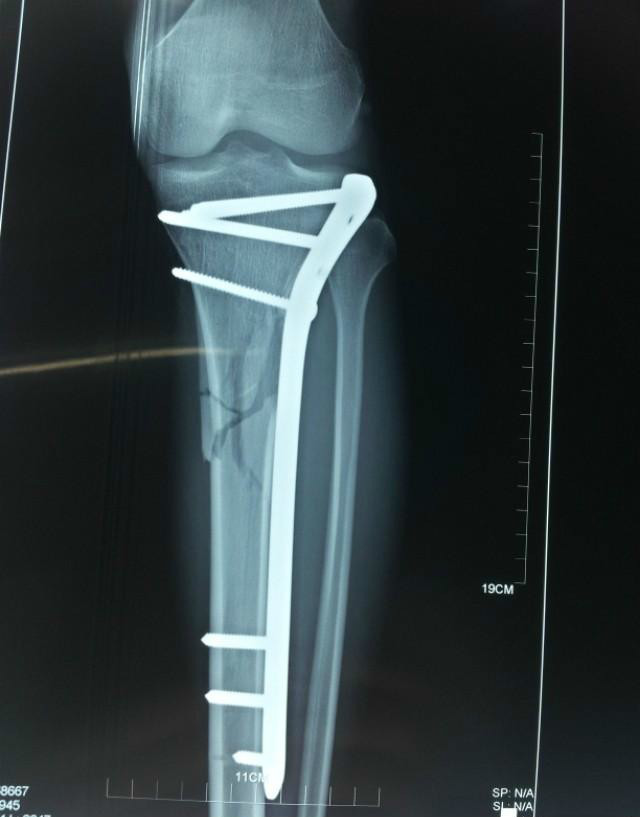

作为医用金属材料,必须满足对人体的适应性、耐腐蚀性、适当的机械强度、表面生物相容性4个最基本的条件。一般材料的机械强度高,拉伸性好,但耐腐蚀性、生物相容性差。目前主要用作接骨板、骨螺钉、齿冠等。由于其表面的生物相容性不理想,常用生物陶瓷HA喷涂或用生物高分子包埋后植于人体中。最常见的喷涂技术,是将HA在1000℃以上的高温下转变成烟雾,直接喷在金属表面形成一覆盖层。

上图为上海硅酸盐所在微生物催化生物陶瓷用于骨再生方面取得的重要进展展示,点击下方链接了解详情。